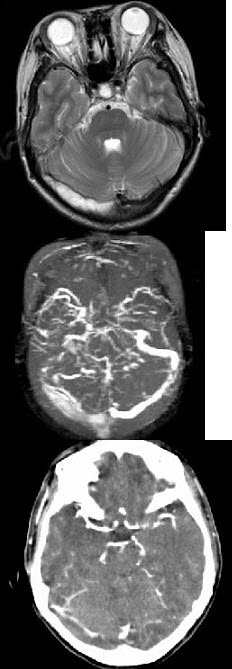

患者,女性,30岁,3年前因为双下肢麻木无力,治疗3周后症状消失。1年前右眼视力下降,未经治疗2周后好转。近1周出现走路不稳、复视。MRI表现如图。 应该给予的辅助检查包括( )

A:头MRI

B:CSFOB检测

C:脊髓MRI

D:诱发电位

E:以上均是